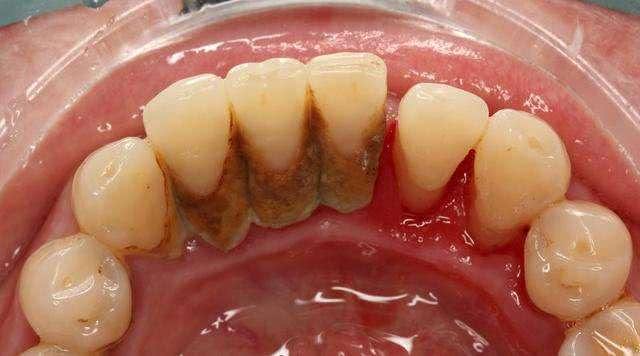

原来患者只是平时口腔卫生没维护好,造成下前牙牙结石堆积,吃饭的时候一不小心出现了“牙结石”脱落。

牙结石是沉积在牙面或修复体表面已钙化或正在钙化的菌斑及沉积物,由唾液或龈沟液中的矿物盐沉积而成。

根据沉积的部位,以龈缘为界,可分为龈上结石和龈下结石。